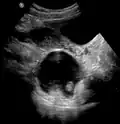

Dermoid cyst in vaginal ultrasonography -

A complex cyst due to a dermoid as seen on ultrasound -